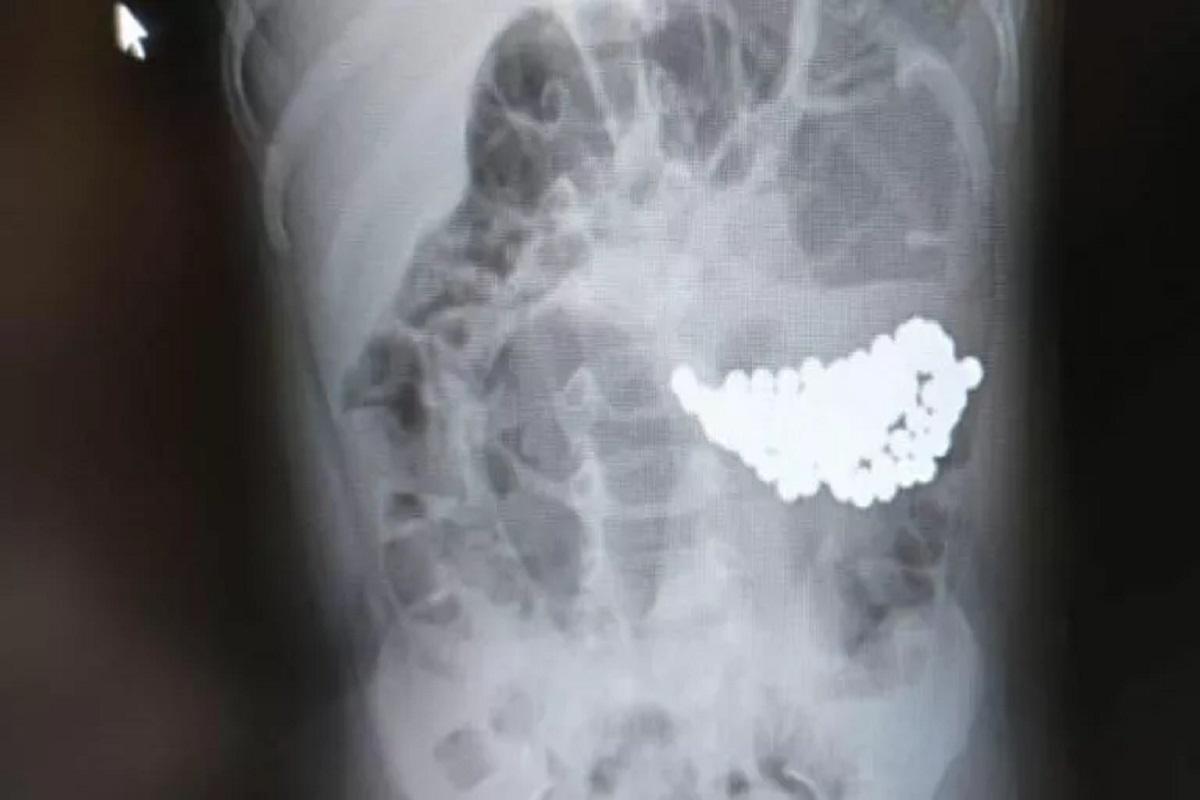

Так, ранее сообщалось о двухлетнем ребенке, проглотившем 100 разноцветных магнитных шариков. Другой малыш играл с металлическим медальоном и случайно проглотил его.